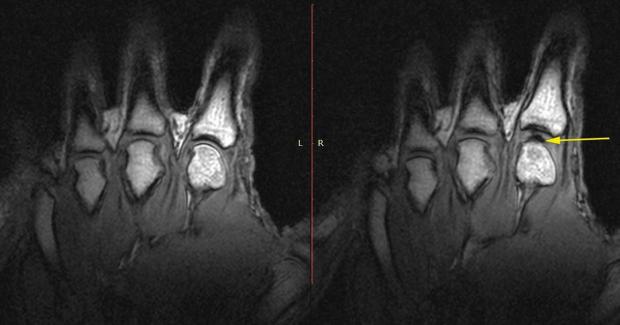

Tuy nhiên đến năm 2015, Greg Kawchuk đến từ Đại học Alberta và các cộng sự của ông đã dùng máy quét MRI để ghi lại xem những gì đã xảy ra bên trong ngón tay của các tình nguyện viên có thói quen hay bẻ đốt ngón tay. Kết quả là những gì bạn có thể nhìn thấy trong hình. Với những gì quan sát được, nhóm chuyên gia lúc bấy giờ kết luận chính sự thay đổi hình dạng của những bóng khí vốn đã tồn tại từ trước đã sản sinh áp suất, từ đó tạo nên âm thanh. Điều mà họ vẫn còn băn khoăn là không biết liệu áp suất đó có đủ lớn để tạo ra vết nứt nào hay không.